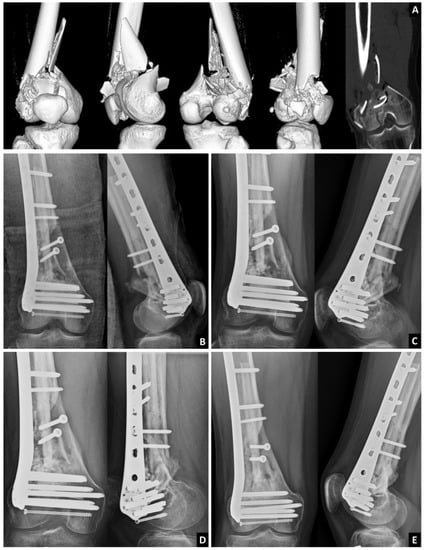

Use of an Intramedullary Allogenic Fibular Strut Bone and Lateral Locking Plate for Distal Femoral Fracture with Supracondylar Comminution in Patients over 50 Years of Age

2.1. Surgical Technique